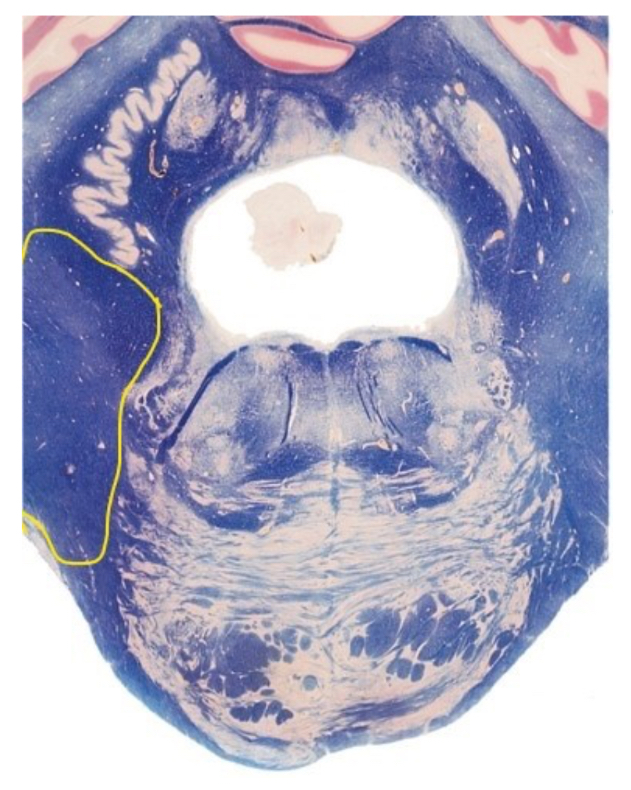

4

Q

This section is through the _________________?

A

rostral pons

7

The highlighted structure is?

middle cerebellar peduncle